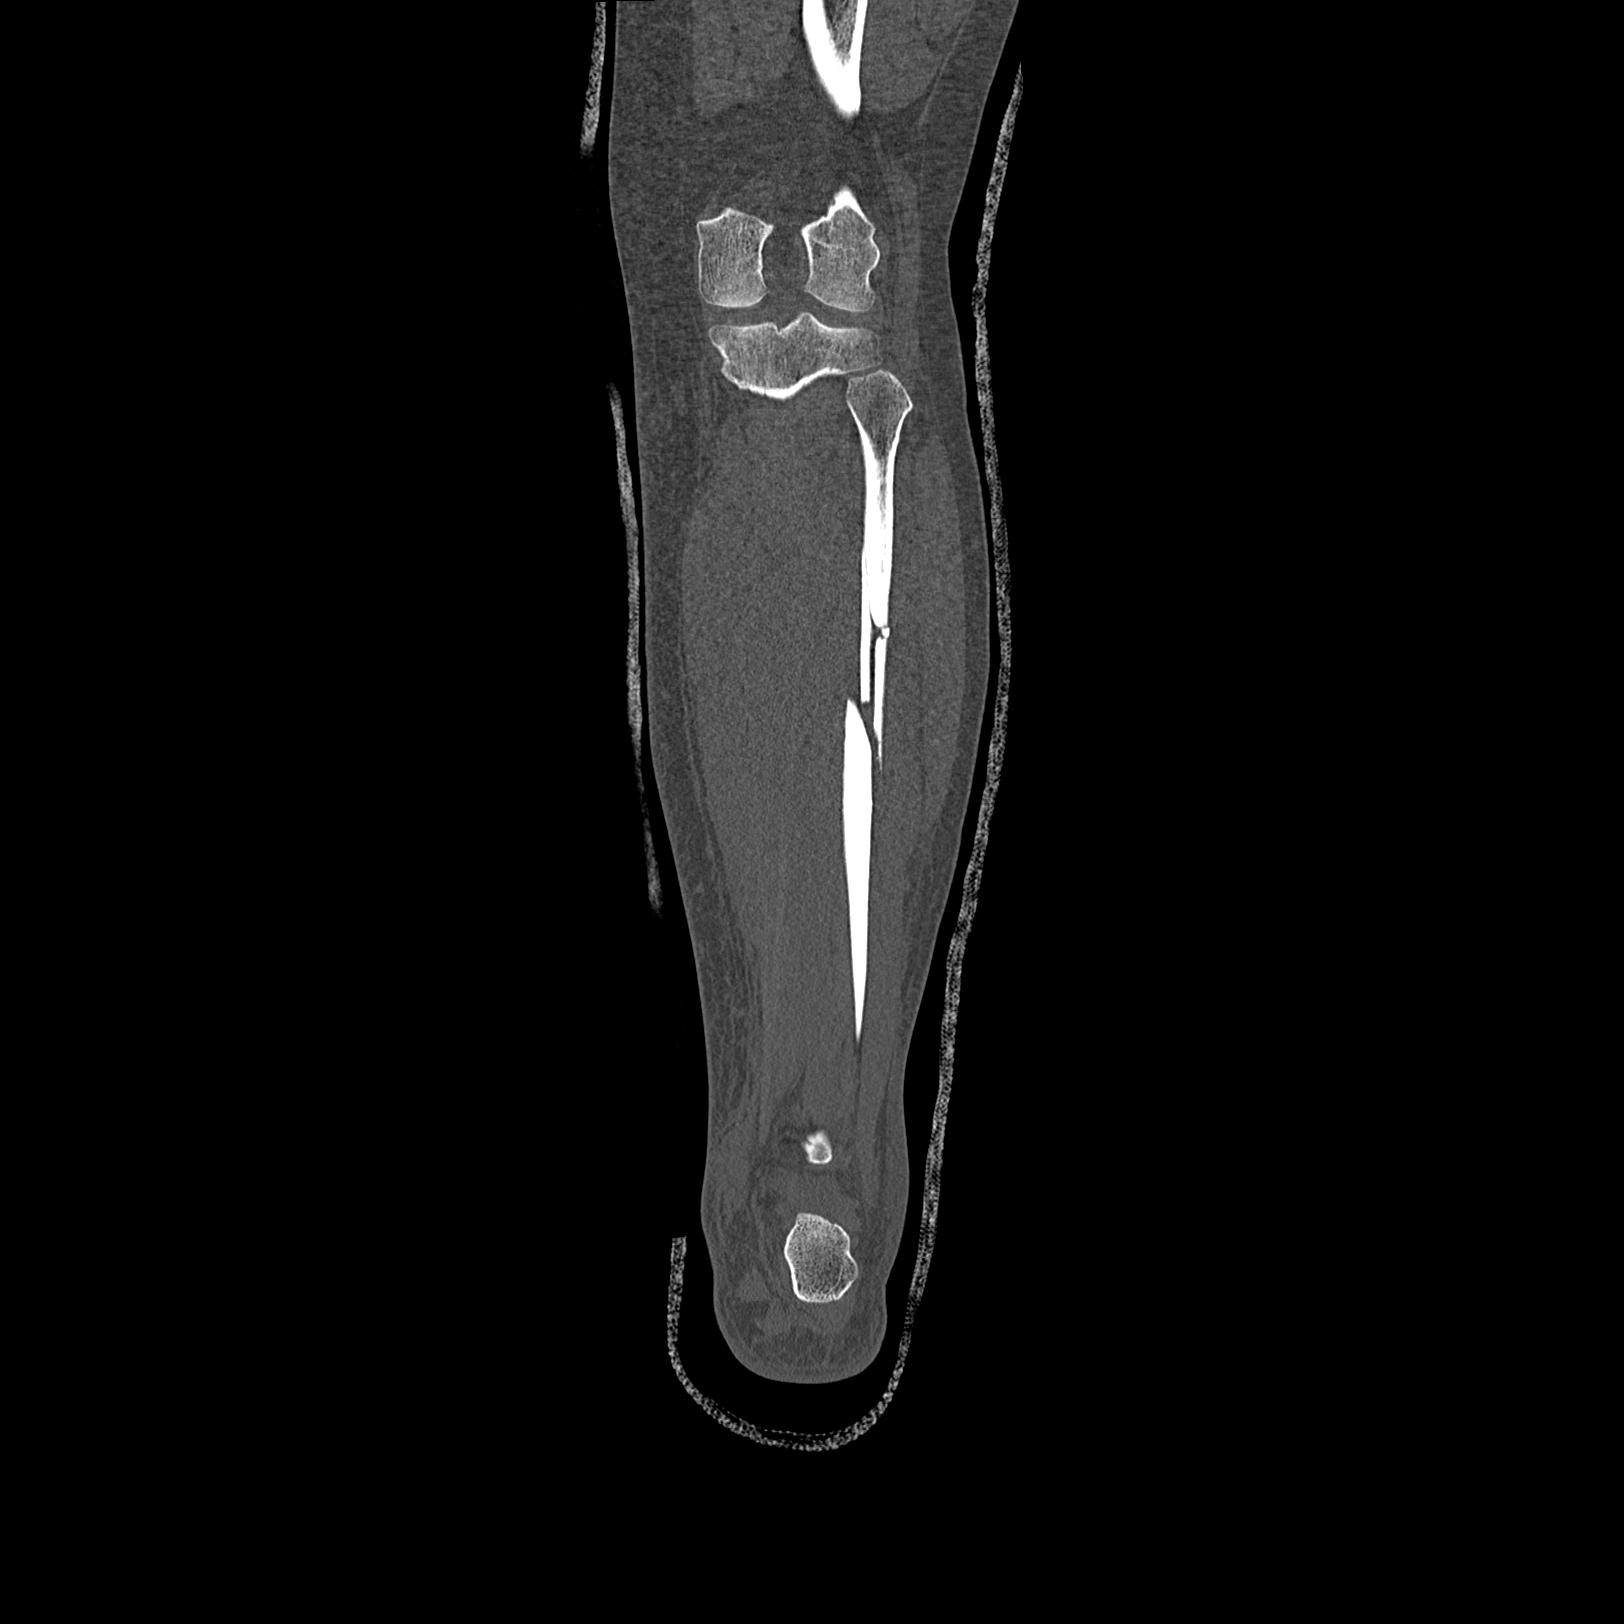

102803 1/12(キウスなし) 1/27 左下腿 4R 30歳女性 左脛骨軸内釘